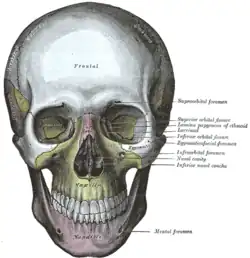

Crânio visto de frente

Crânio visto de frente -